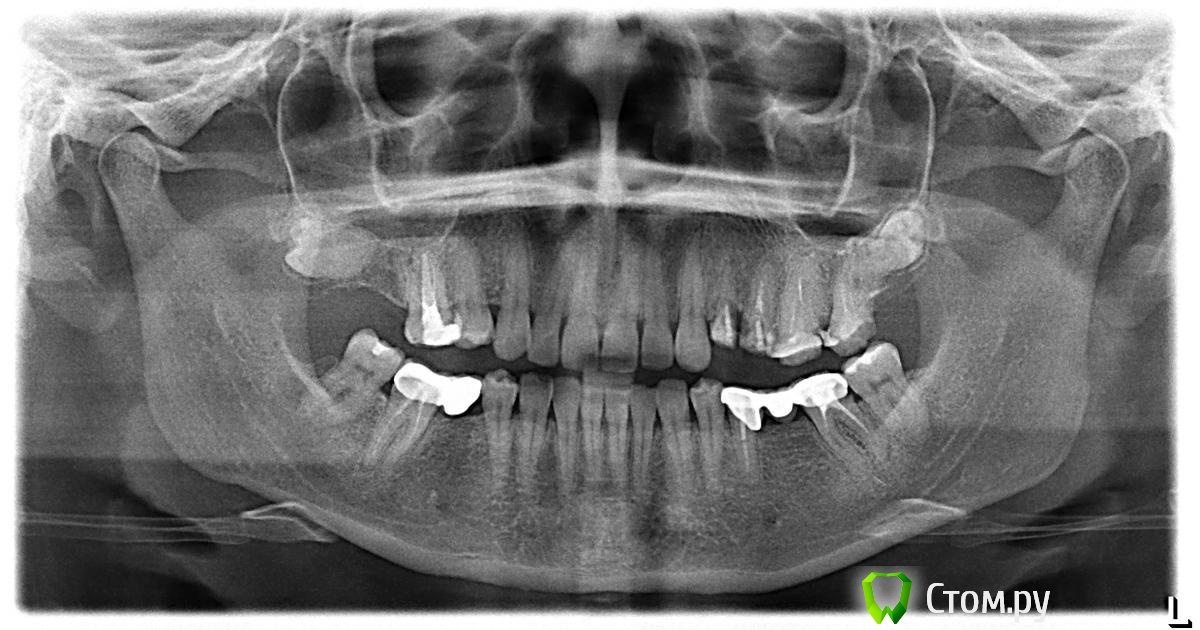

Барни Опубликовано 4 мая, 2014 Поделиться Опубликовано 4 мая, 2014 Здравствуйте! Помогите, пожалуйста, определиться с планом лечения и протезирования зубов по приложенному снимку.Женщина, 36 лет.1. Если возможно подскажите, какие зубы необходимо удалять из-за корневых и межкорневых кист?2. Какие зубы можно сохранить с обязательным перелечиванием каналов (сказали, что все залеченные каналы сделаны плохо и из-за этого вызвали воспаление и образование кист)?3. Возможно сделать протезирование с помощью металлокерамических коронок без использования имплантов?4. Как лучше сделать протезирование с помощью коронок (проблема в том, что зубы короткие и все коронки слетают, до этого врач нашел выход – загонял коронку под десну, но у меня почему-то постоянно под коронку попадала пища и воспалялись десны, другой доктор сказал, что таким образом коронки ставить нельзя)?Есть КТ, по необходимости могу сбросить.Заранее благодарна за ответ. Ссылка на комментарий

Гарриевич Опубликовано 4 мая, 2014 Поделиться Опубликовано 4 мая, 2014 1. Удалять нужно ретенированный зуб на в/ч справа и под вопросом 4 и 5 зубы в/ч слева2 перелечивать 6,7 слева вч, 5,7 слева нч, 7 справа нч3 возможно, для этого нужно будет депульпировать 5 справа нч и взять 5 и 7 под опоры мостовидного протеза4 хороший ортопед и проблем не будет ПС импланты предпочтительнее. У вас развернут 5 зуб на вч справа и далее зубов нет, вот этот дефект просто коронками не восстановишь, либо имплантация либо съемный протез Ссылка на комментарий

Гарриевич Опубликовано 4 мая, 2014 Поделиться Опубликовано 4 мая, 2014 Добавлю, если 4,5 зубы на вч слева удалятся, мостовидный протез там более не желателен, чем на нч 1 Ссылка на комментарий